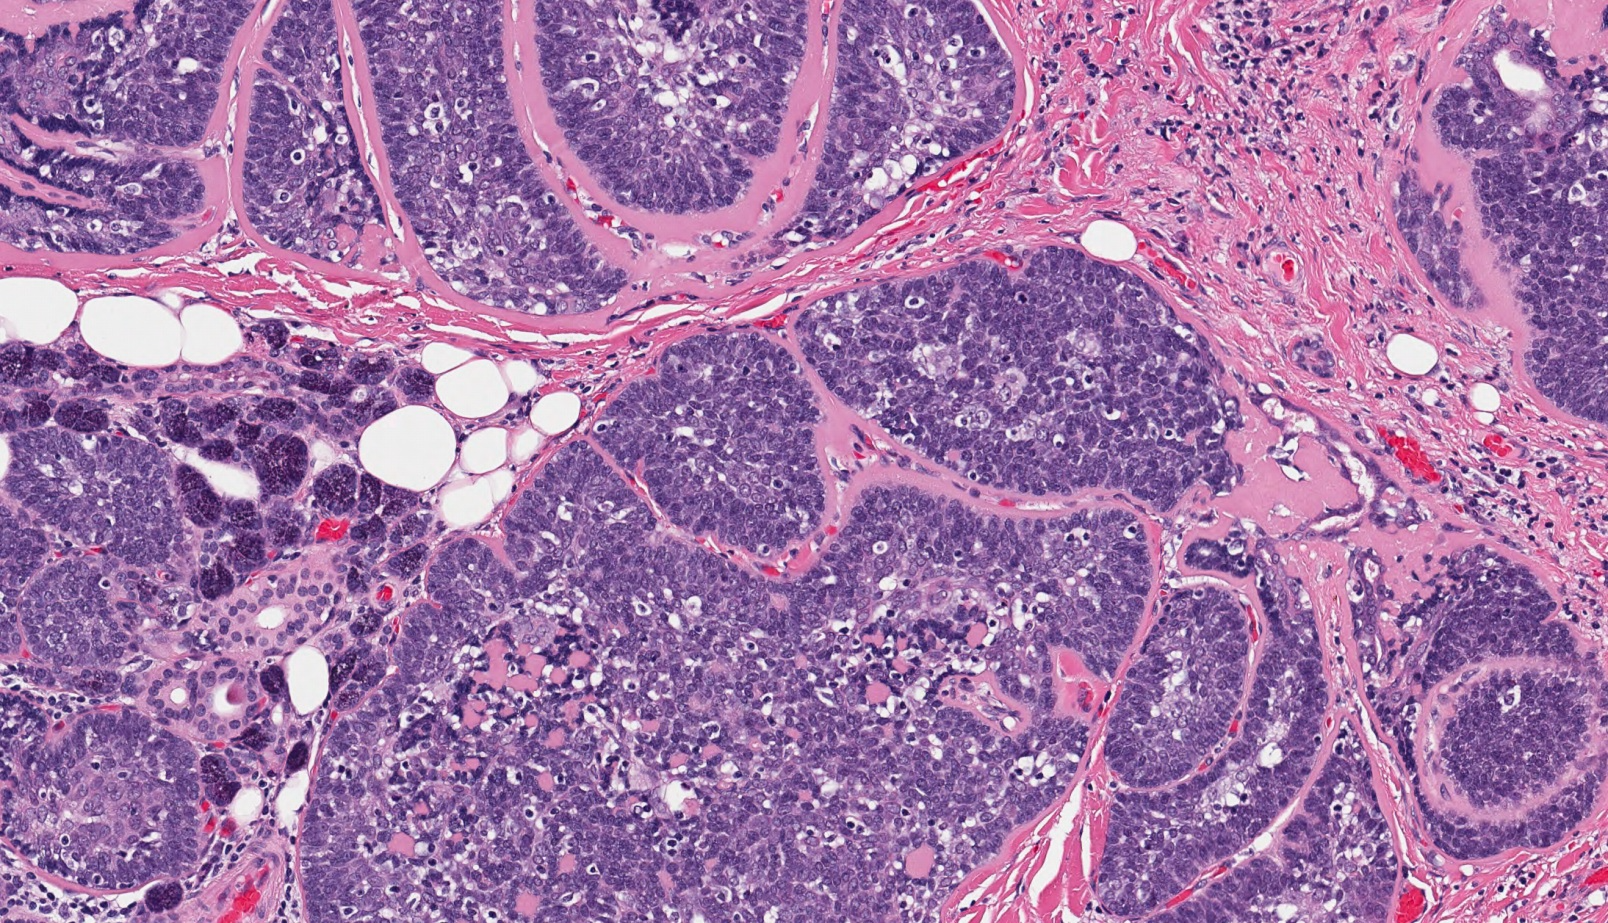

Acinic Cell Carcinoma (AcCC)

Acinic cell carcinomas account for 1-6% of salivary gland tumours.